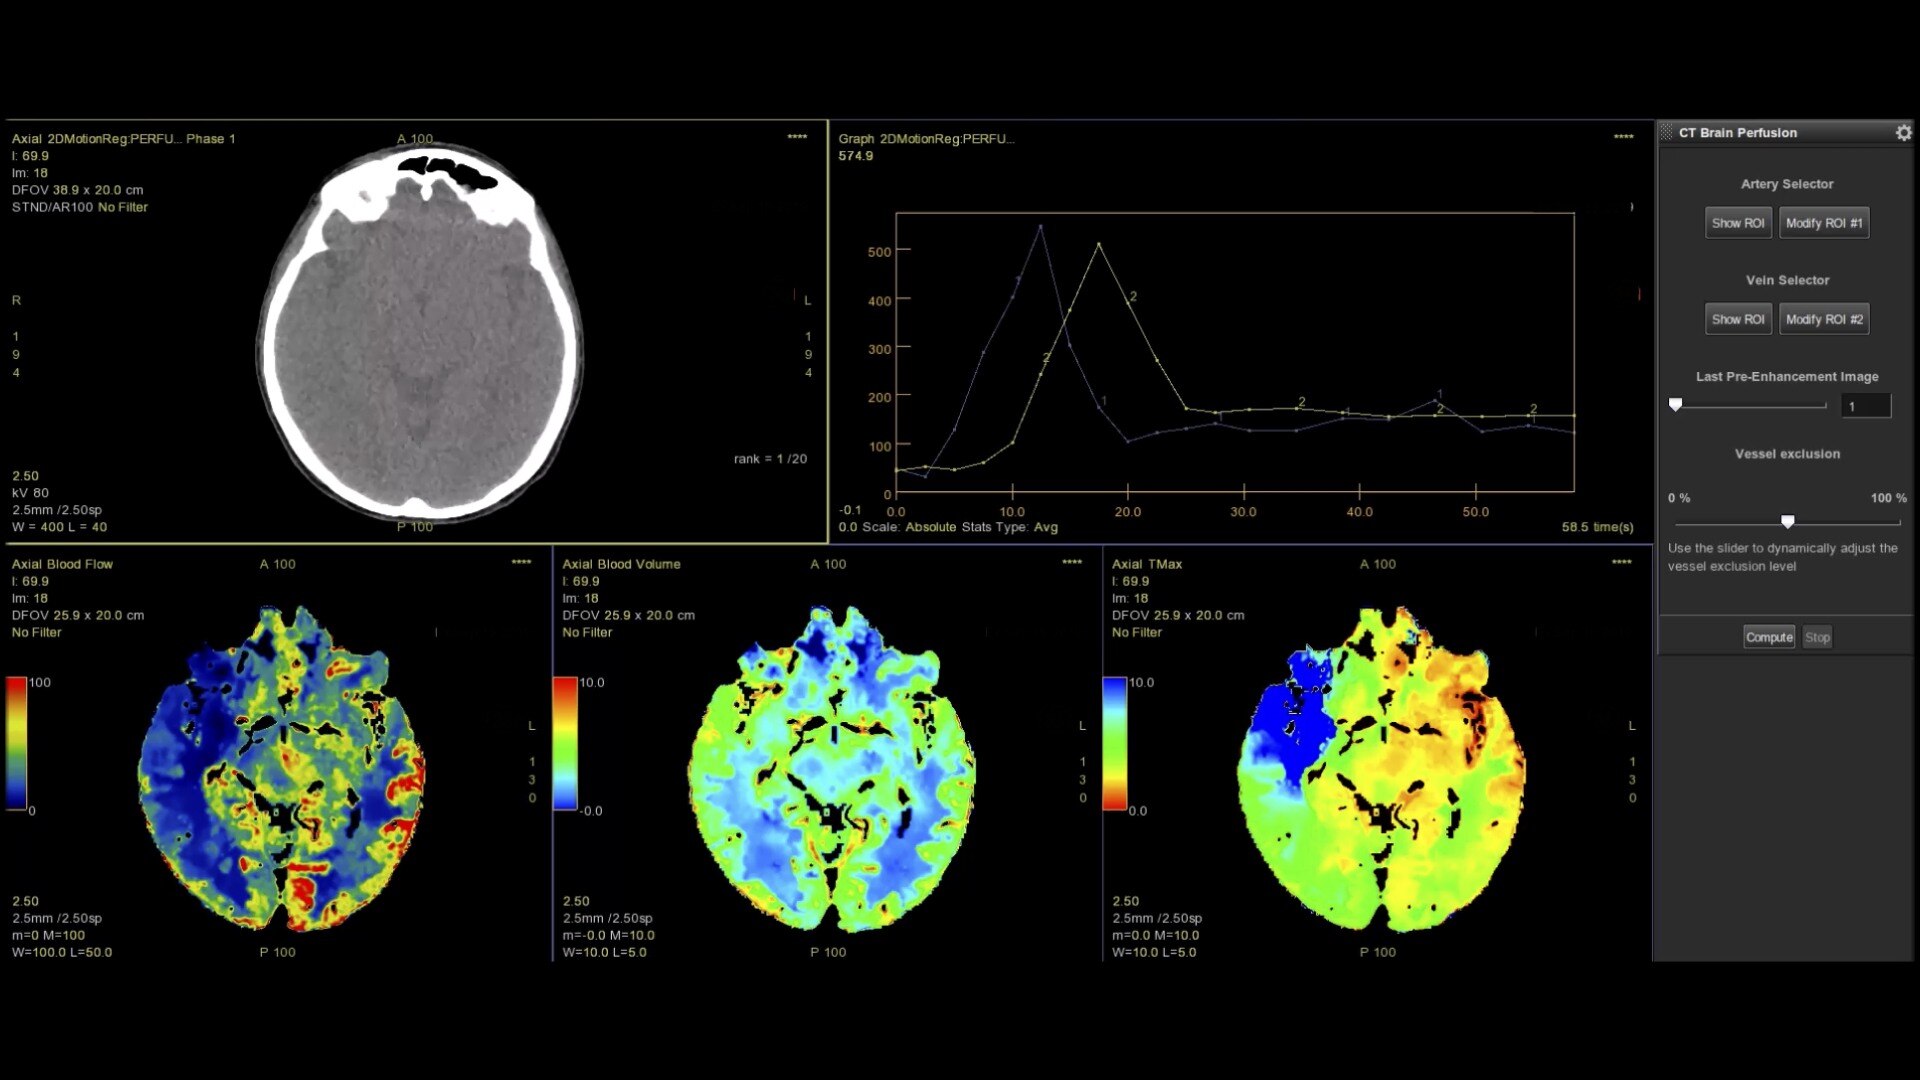

Brain perfusion

Easy-to-use automated workflow for CT stroke and tumor angiogenesis evaluation

Brain stroke protocol

• Image Registration to minimize the effects of patient movement

• Bone Removal to remove the cranium automatically from the dataset

• Deep Learning brain ventricle segmentation to prevent ventricular matter inclusion in quantitative results and improve visual inspection of the maps

• Automated selection of arterial input and venous output. Both can be easily adjusted if needed.

• Automated generation of all functional maps: Blood Flow, Blood Volume, Mean Transit Time, and Transit Time to IRF Peak (Tmax)

• Automatically define the symmetry plane to be used for mirroring ROIs and relative thresholds

• Tissue Classification enables the visualization of regions that are segmented from absolute or relative values, customizable thresholds and user selectable input maps

• Mismatch volume and ratio are calculated from the modified perfusion volume and low perfusion volume ROIs